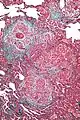

| High magnification photomicrograph of a lung biopsy taken showing chronic hypersensitivity pneumonitis (H&E), showing mild thickening of the walls of the small air sacs by invasion of white blood cells. A multinucleated giant cell, seen within the walls of the air sacs to the right of the picture halfway down, is an important clue to the correct diagnosis. | |

Lung biopsy

Lung biopsies can be diagnostic in cases of chronic hypersensitivity pneumonitis, or may help to suggest the diagnosis and trigger or intensify the search for an allergen. The main feature of chronic hypersensitivity pneumonitis on lung biopsies is expansion of the interstitium by lymphocytes accompanied by an occasional multinucleated giant cell or loose granuloma.[7][22]

When fibrosis develops in chronic hypersensitivity pneumonitis, the differential diagnosis in lung biopsies includes the idiopathic interstitial pneumonias.[23] This group of diseases includes usual interstitial pneumonia, non-specific interstitial pneumonia and cryptogenic organizing pneumonia, among others.[7][22]

The prognosis of some idiopathic interstitial pneumonias, e.g. idiopathic usual interstitial pneumonia (i.e. idiopathic pulmonary fibrosis), are very poor and the treatments of little help. This contrasts the prognosis (and treatment) for hypersensitivity pneumonitis, which is generally fairly good if the allergen is identified and exposures to it significantly reduced or eliminated. Thus, a lung biopsy, in some cases, may make a decisive difference.